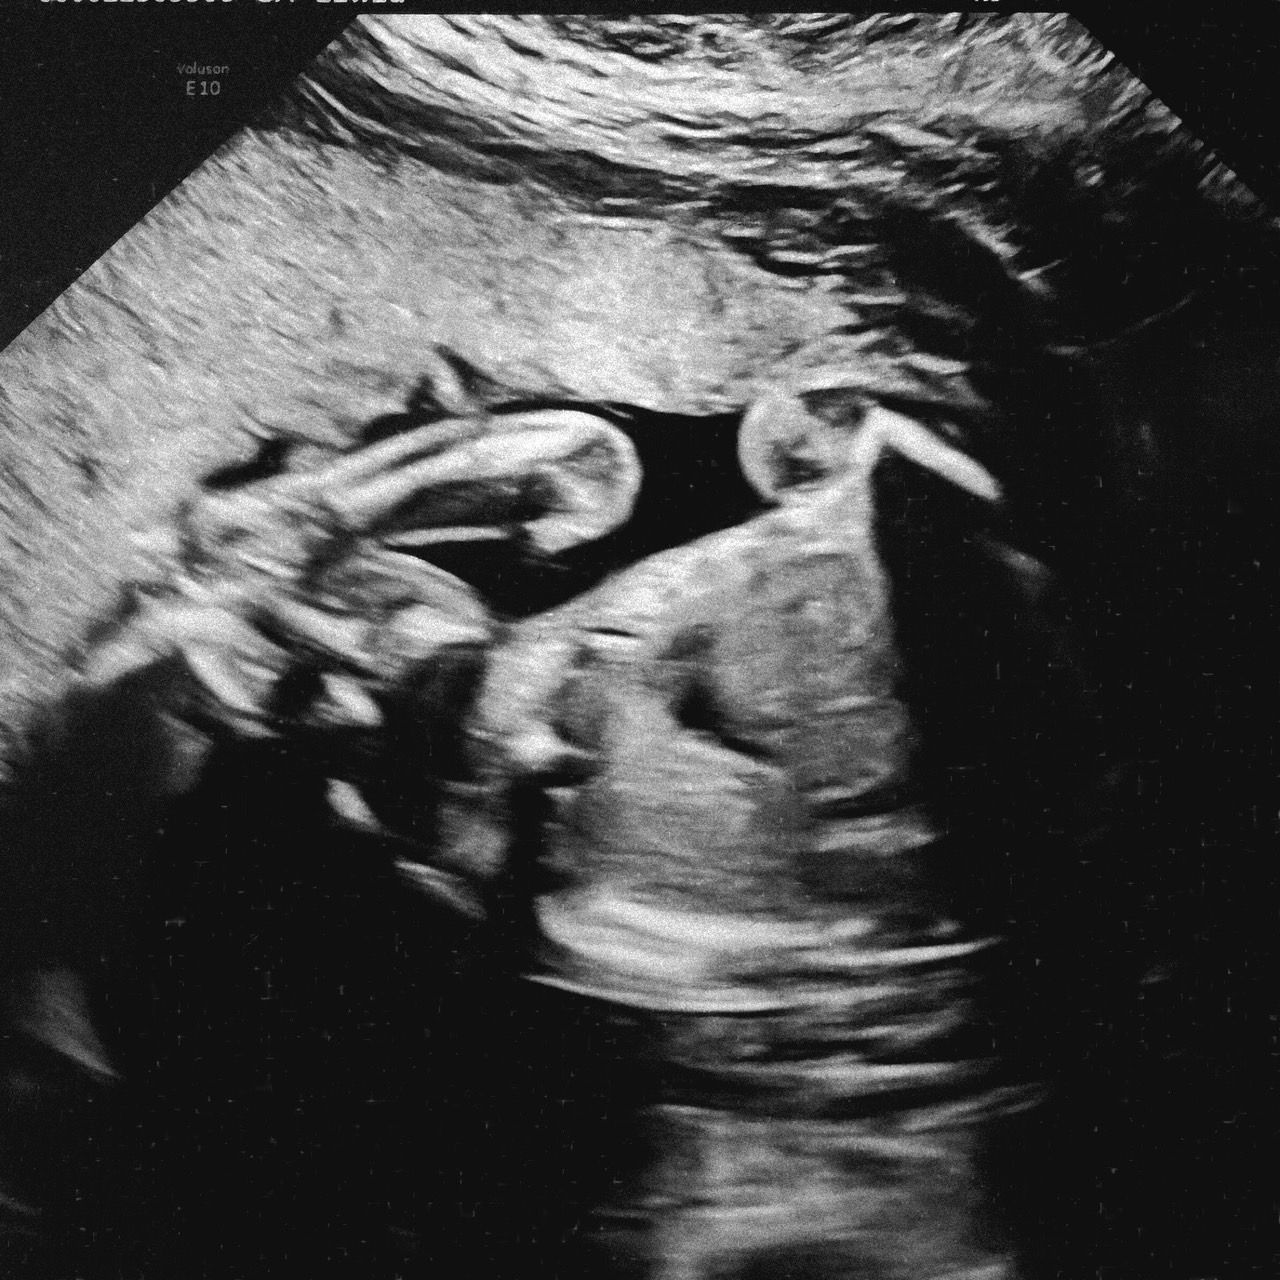

給大家看看今天技師 Karen 幫我們照的超音波照片,雖然當時螢幕上明明就有好多好多好好看的照片,但我不知道她怎麼給我挑了這幾張啦!

這張是寶寶 22w2d 躺著手抓頭的模樣

這張其實也是寶寶 22w2d 躺著手抓頭的模樣,只是角度有一些些不同